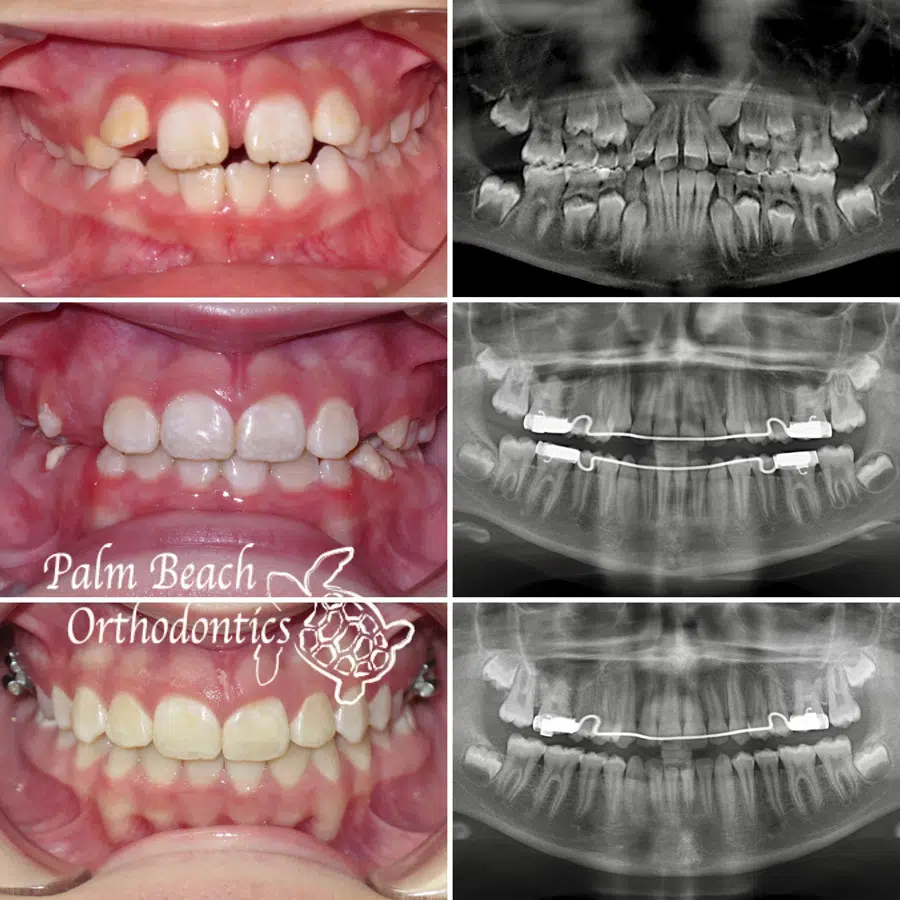

Before and After

Incredible results and inspiring journeys; see some of our patients’ before and after photos next time you visit our practice.